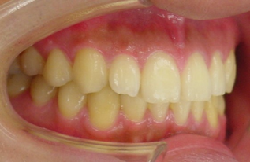

初診時

治療途中

当矯正歯科医院では、マルチループ(MEAW法)を利用して上顎前突(出っ歯)や咬合高径(咬み合わせの高さ)の改善をしています。